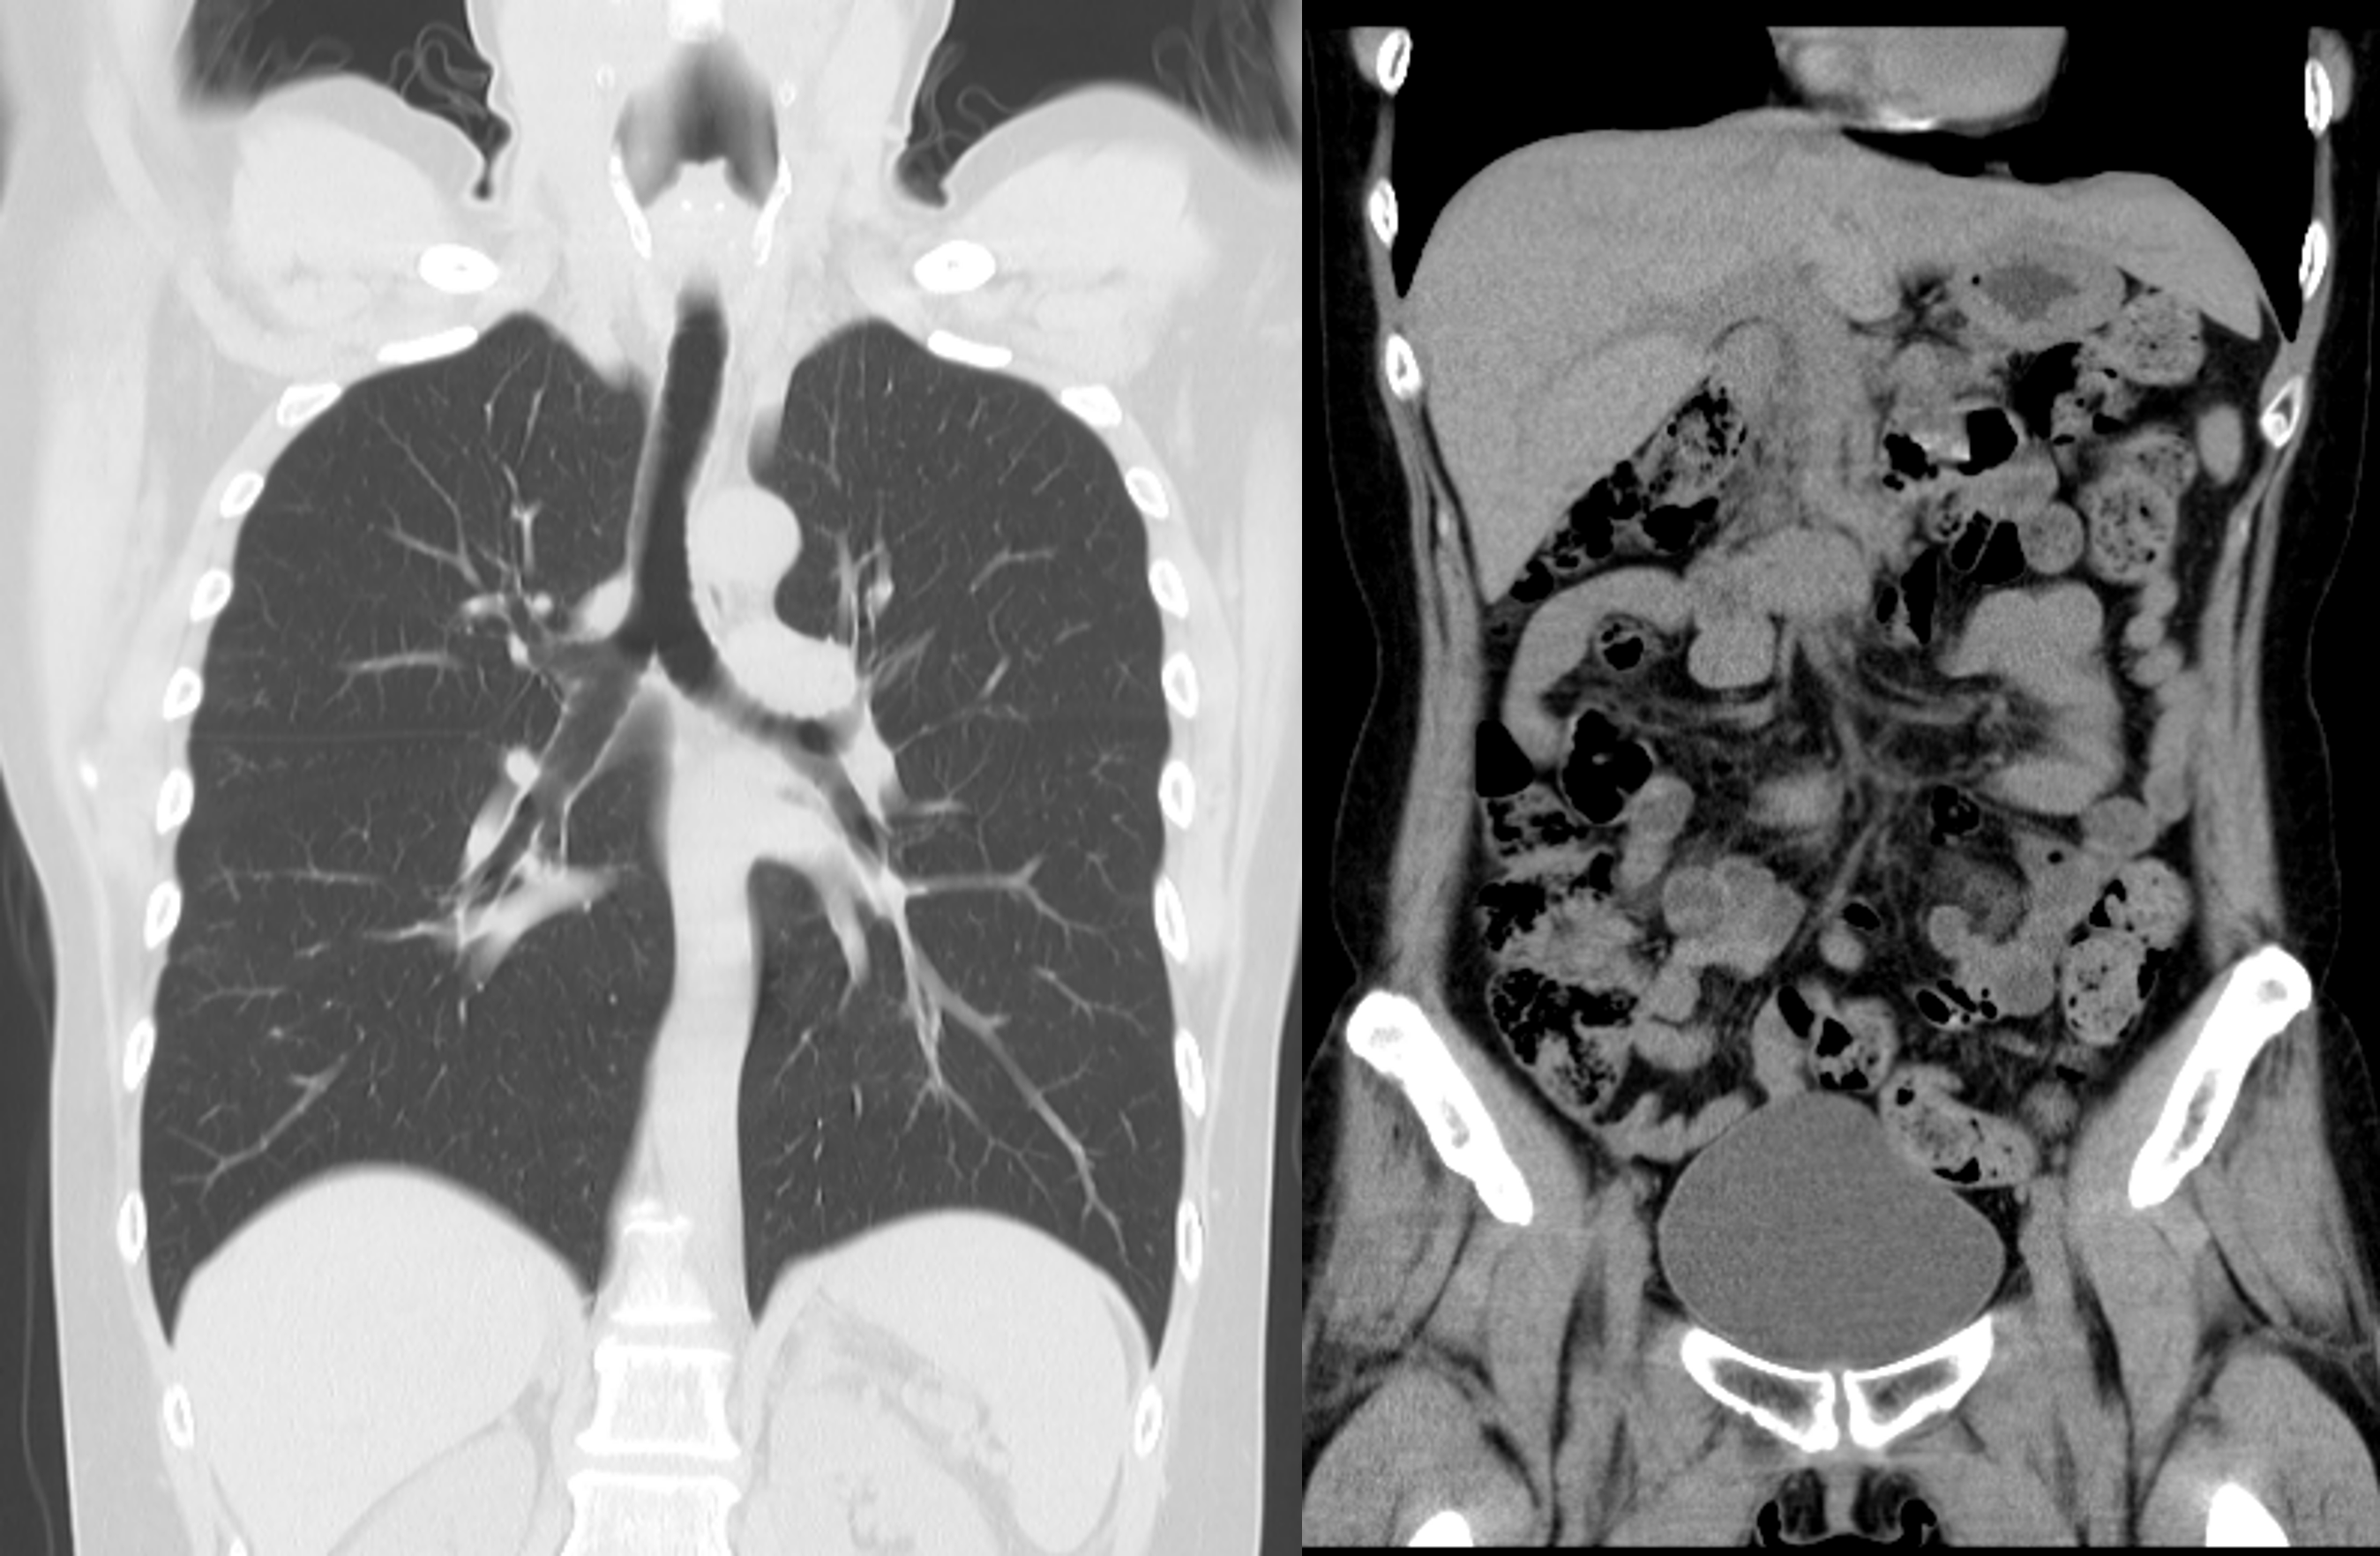

肺がんは日本人男性において最も患者数の多いがんです。喫煙との関係が非常に深いがんですが、たばこを吸わない人でも受動喫煙により発症リスクが高まることもわかっています。肺がんも初期ではほとんど症状がなく、早期発見には肺CT検査が最も有効です。最新のCTでは、超低線量での撮影が可能で、被ばく量は従来の胸部X線1枚分とほぼ同等です。

胸部CT(低線量CT)

5分程度

当院では、被ばく量の少ない低線量CTによる検査を行っています。

低線量CTでは従来の胸部単純X線(レントゲン)検査に比べ早期の肺がんを見つけることが可能で、がんの正確な部位、大きさ、周囲臓器への拡がりやリンパ節への転移の有無など、レントゲンではわからない病変を調べます。寝台に仰向けで寝ていただき、合図に合わせて数秒程度の息止めがあります。

検査日から1週間後を目安に郵送いたします。

医師による検査結果を当日ご希望の場合は、検査後30分程度お待ちいただきます。

胸腹部ドックは胸部から骨盤にかけての検査です。胸部領域は空気を含むためMRIでの評価が困難であり、CTで検査を行います。肝臓や膵臓や腎臓などの腹部領域も同時に評価することができます。CTの検査時間は5分程度ですので、短時間で幅広い部位を検査をしたい方におすすめしています。また、撮影したCT画像を用いて内臓脂肪測定も行っており、これはメタボリックシンドロームの指標にもなっていますので、 肥満を気にされている方にもおすすめです。

●CT(胸腹部~骨盤)+採血(腫瘍マーカー8項目+一般項目(アミラーゼ・トリプシン・HbA1c・肝機能・血液一般+感染症)

15分程度

検査日から2~3週間後を目安に郵送いたします。

医師による検査結果をご希望の場合は、後日受診してください。(保険診療)